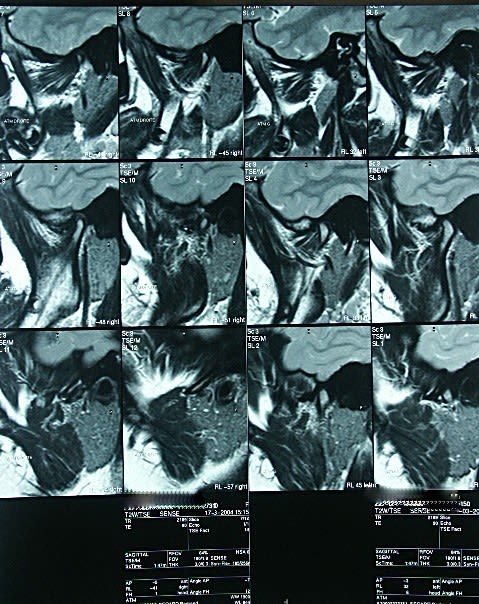

Compte rendu de l'IRM des ATM:

- protocole: séquences dynamiques en sagittales droite et gauche, et réalisation de séquences sagittales en T2.

- résultat: sur les séquences T2, il n'y a pas dépanchement intra-articulaire. Le ménisque gauche est correctement situé et sa mobilité est satisfaisante lors de l'ouverture de la bouche. A droite, il semble exister une désinsertion postérieure du ménisque qui se luxe antérieurement, particuliérement lors de l'ouverture de la bouche.

- Conclusion: la subluxation antérieure de la bouche ouverte se fait normalement: la ménisque gauche présente une cinétique normale, tandis que le ménisque droit semble présenter une luxation antérieure.

Sur cervicales:je considère que la posture n'est pas au top,mais bon...

Sur le 5ème et 8ème cliché,je devine une postériorisation du condyle,donnant une compression de la zône bilaminaire,qui a l'habitude de générer beaucoup de symptômes.

Le reste est ininterprètable pour moi sur ces retransmissions,atm et ménisques très flous.